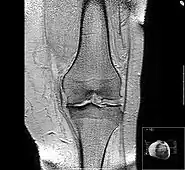

Diagnosis is made with reasonable certainty based on history and clinical examination.[51][52] X-rays may confirm the diagnosis. The typical changes seen on X-ray include: joint space narrowing, subchondral sclerosis (increased bone formation around the joint), subchondral cyst formation, and osteophytes.[53] Plain films may not correlate with the findings on physical examination or with the degree of pain.[54]

MRI of osteoarthritis in the knee, with characteristic narrowing of the joint space